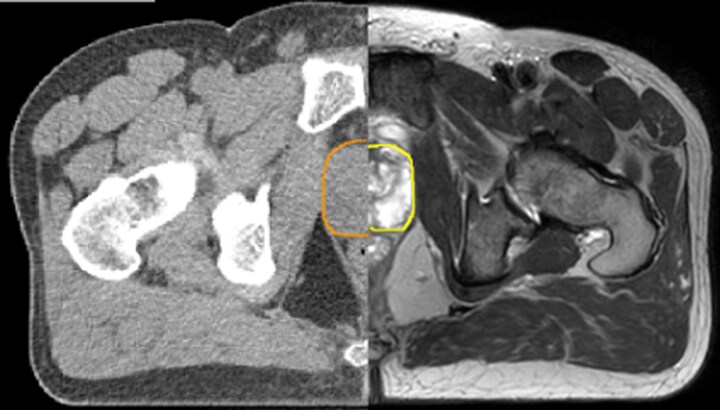

With its superior soft tissue contrast compared to CT, MRI offers exquisite visualization of tumor boundaries and proximity to nearby critical structures.

The ability to tune contrasts can provide even more valuable information about tumor characteristics and tumor extent to facilitate enhanced delineation, and also provides possibilities for dose boosting strategies.

Diffusion-weighted imaging (DWI) for example depicts areas of high signal intensity in soft tissues that are indicative of the restricted water mobility (i.e., diffusion) of a tumor and can also be used to identify lymph nodes. Changes in the tissue’s or lesion’s apparent diffusion coefficient (ADC) can provide insights that help predict the tumor’s response to radiotherapy.